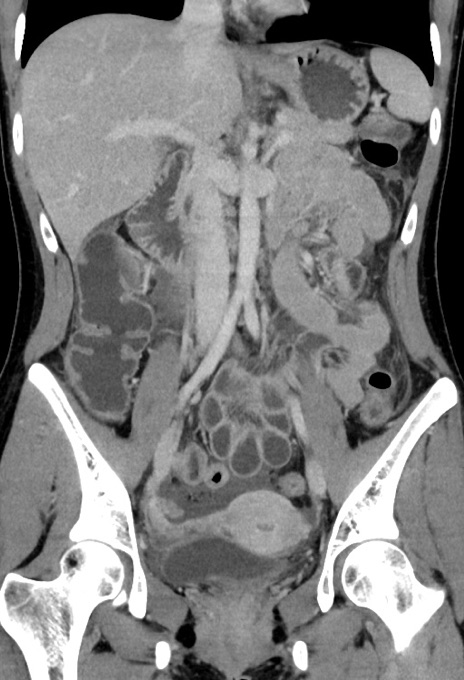

症例17(冠状断像)

【症例】20歳代女性

【主訴】嘔吐、下腹部痛

【現病歴】昨日夕食後に嘔吐し下腹部痛が出現。本日になっても嘔吐持続し改善しないため来院。

【身体所見】意識清明、BT 37.2℃、BP 108/67mmHg、腹部:平坦、やや硬、下腹部正中から右にかけて圧痛あり、反跳痛軽度あり、tapping pain(+)。

【データ】WBC 13600、CRP 14.94